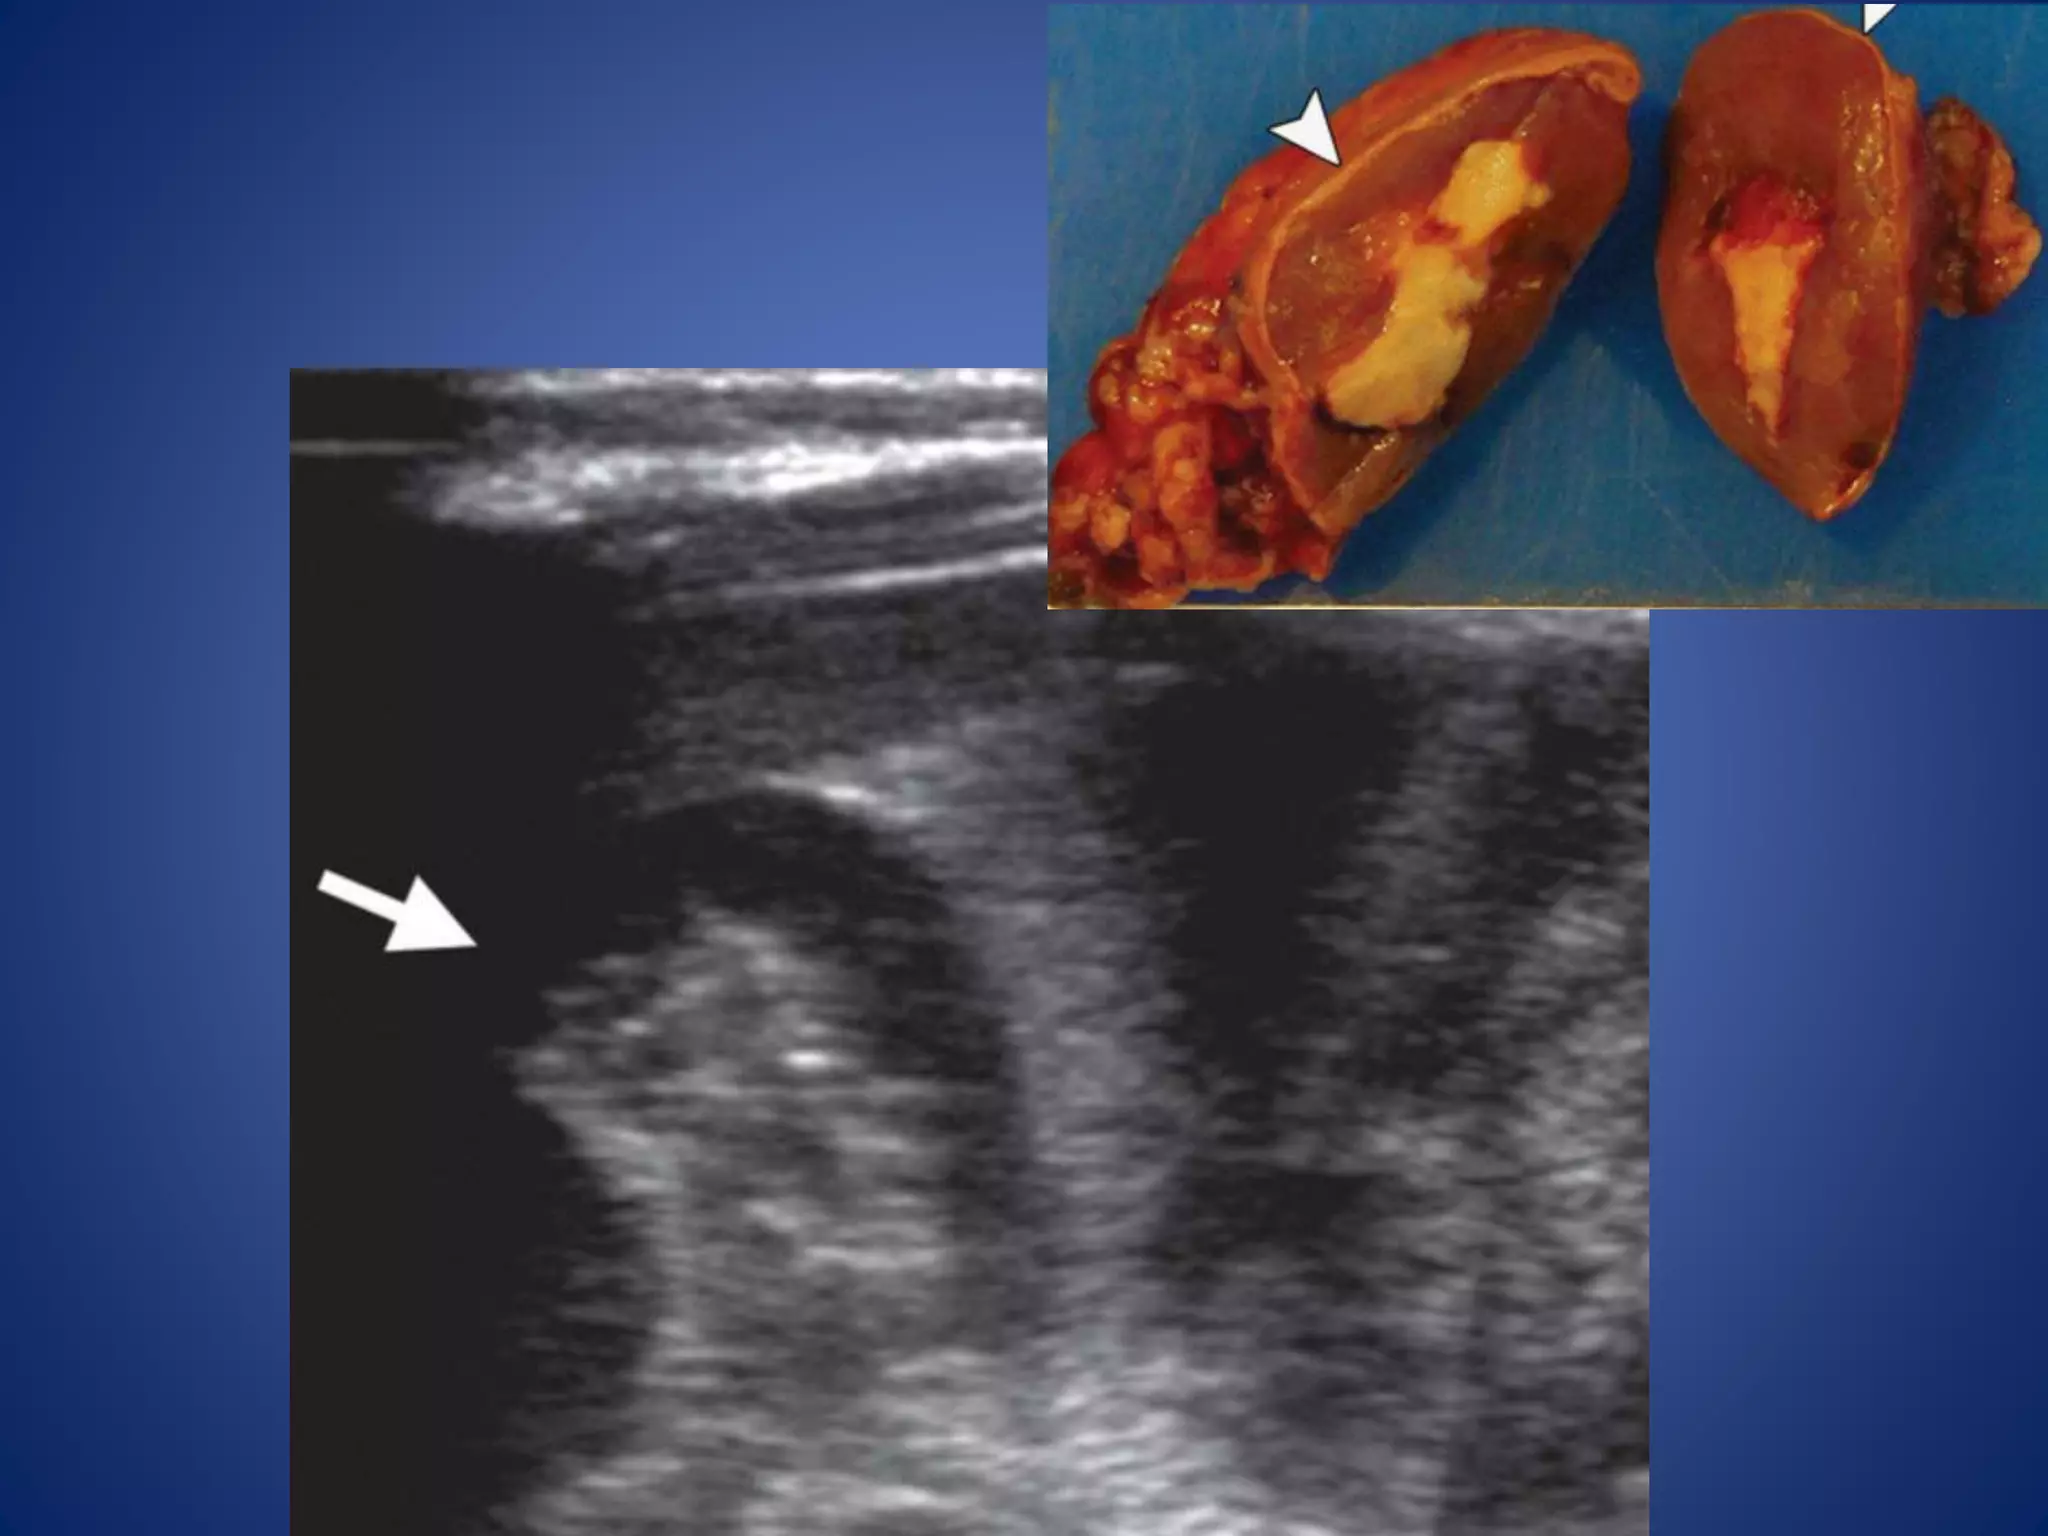

• 31.

Smaller lesions arehomogeneous, whereas larger lesions appear heterogeneous due to central necrosis, hemorrhage, and calcification. Prominent radiating fibrous bands may create a nodular appearance or the appearance of a characteristic stellate scar.

• 32.

At US, smallerlesions are generally homogeneously hypo- or hyperechoic. Larger lesions may have a more heterogeneous nodular appearance or may contain central or diffuse hypoechoic areas corresponding to necrosis. The mass may be surrounded by a hyperechoic, capsule-like rim. Use of color Doppler imaging is helpful in evaluating for caval extension of tumor

• #36 Fetal subtype ACN in a 2-week-old male neonate. (a) Transverse US image reveals a well-circumscribed hypoechoic mass (arrow) with an irregular hyperechoic central focus corresponding to yellow necrosis.

• #37 Post-contrast: well-circumscribed mass (arrow) with an irregular, hypoattenuating central focus of necrosis.

• #38 ACN in an 18-month-old boy with isosexual precocious puberty and Cushing syndrome. Postcontrast: shows the tumor with an enhancing rim (arrowheads).